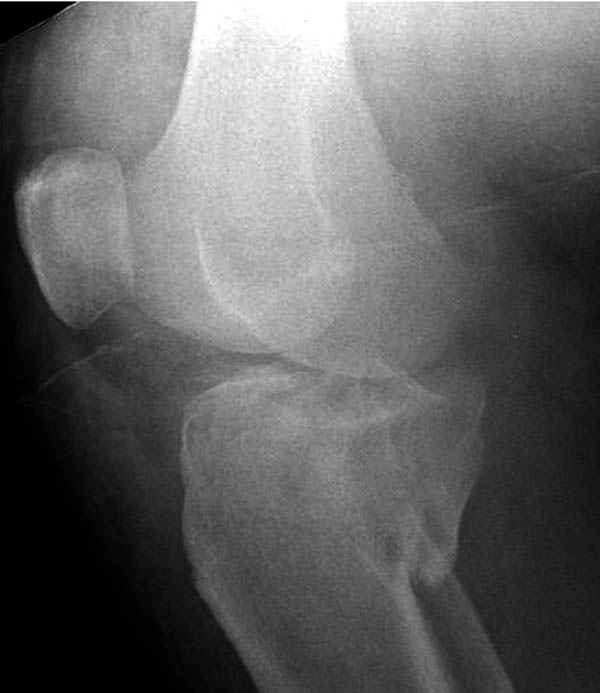

Трудно поверить, что разрекламированная Ортопедическая школа Восточной Украины позволяет такие странные снимки? На прямом снимке сохранен общий контур плато, но не известна судьба импрессии суставной поверхности. На полубоковой?, оставлен без репозиции задне-медиальный отдел, и навряд ли после такой фиксации можно удовлетвориться результатом.

На представленных предоперационных срезах КТ огромный задне-медиальный фрагмент расположен больше кзади, чем медиально. Для планирования, кроме поперечных срезов, надо ориентироваться на корональные срезы, которые укажут топографию верхушки медиального фрагмента.

Доступ к медиальной стороне задний или медиальный, через pes или в пространстве между medial gastroc мышцы.

Надеюсь, представленные снимки разных случаев помогут разобраться в тактике, и критика примется без личной обиды.